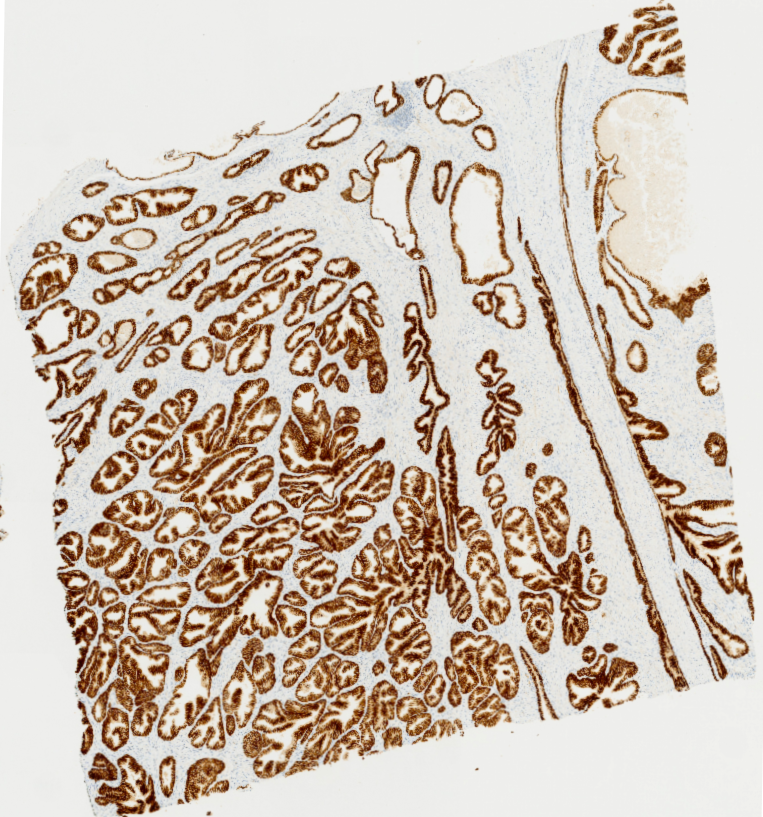

Los escáneres o digitalizadores de láminas son microscopios automatizados capaces de capturar imágenes digitales idealmente en alta resolución a partir de láminas histológicas físicas. Existen distintos modelos según el volumen y la aplicación clínica, pero para diagnóstico deben cumplir estándares estrictos de calidad y precisión.

Digitalizamos tus láminas y entregamos archivos listos para diagnóstico, revisión o docencia, con imágenes de alta resolución que cumplen estándares internacionales y que pueden ser fácilmente integradas por sistemas LIS.

Acceso a imágenes listas para revisión, discusión de casos y telepatología.